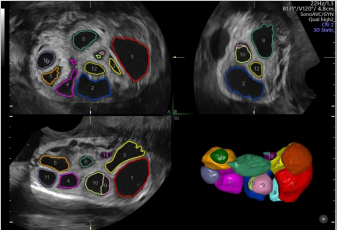

卵泡自動(dòng)監(jiān)測

能夠自動(dòng)計(jì)算受激卵泡數(shù)量和體積并排序,幫助快速識(shí)別優(yōu)勢卵泡。

通過自動(dòng)的放置取樣框綠線并根據(jù)胎兒活動(dòng)自動(dòng)調(diào)節(jié),使得容積圖像的獲取更簡單快速。